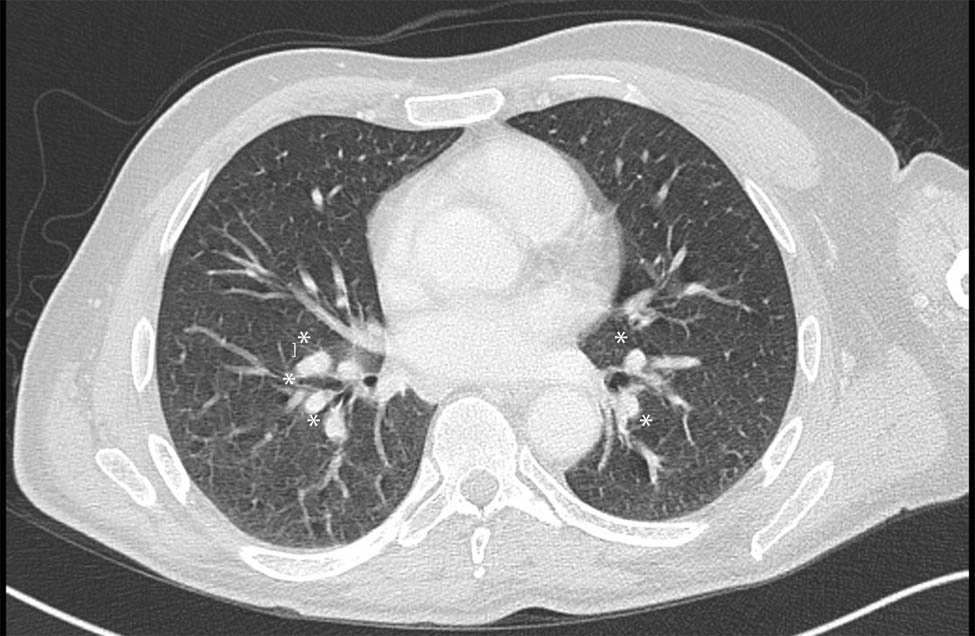

Cervical and dorsal spine MRI showed a hyperintensity area extended from C5 to D2 on T2-weighted images, involving both the gray and white matter. Post-contrast scans revealed inhomogeneous enhancement of the lesion, distributed both in the dorsal subpial space and inside the central canal (Figure 1). Brain MRI resulted negative.

(a–d) Spinal MRI at clinical onset. (b) Sagittal T2-weighted image showing the hyperintense lesion extending from C5 to D2 (asterisks); (c) Sagittal T1 post-contrast sequence showing posterior subpial contrast enhancement (asterisks). Axial T1 post-contrast (a) and t2-weighted (d) sequences at symptoms’ onset showing the “trident sign” (asterisk). (e and f) spinal MRI 6 months after treatment. Sagittal T2-weighted (e) and T1 post-contrast (f) sequences showing an almost complete disappearance of the spinal lesion.

The patient was treated with high doses of intravenous corticosteroid therapy for 5 days (methylprednisolone 1 g per day) and after discharge with tapering doses of oral corticosteroids starting from prednisone 50 mg per day with slow reduction until suspension after 9 months. A new MRI of the cervical and dorsal spine was performed 6 weeks later showing the almost complete disappearance of the inflammatory lesion and the absence of contrast enhancement (Figure 1). Mycophenolate mofetil was added 3 months later. A thoracic CT scan performed 1 year later showed the reduction in the mediastinal and hilar lymph nodes. No clinical or radiological relapses were reported in the two following years.

Alike sarcoidosis, the imaging spectrum for spinal sarcoidosis is wide, but most commonly includes smooth or nodular leptomeningeal enhancement with patchy peripheral cord enhancement, due to inflammatory infiltration of the perivascular spaces. Isolated involvement of the spinal cord is rare (<0.5% of sarcoidosis cases) and linear dorsal subpial enhancement can be present at the MRI [27,28]. A combination of linear dorsal subpial and central canal enhancement in axial sequences depicts the so-called trident sign. This peculiar MRI feature is now widely accepted as a clue sign of spinal cord sarcoidosis and may offer valuable support in doubtful cases [29]. In this regard, it is indicative in the case reported by Jolliffe et al., who described a patient affected by LETM initially diagnosed as NMOSD because of a positive ELISA testing for anti-AQP4 IgG, but in whom detection of the trident sign in the spinal MRI finally led to the corrected diagnosis of spinal cord sarcoidosis [30].